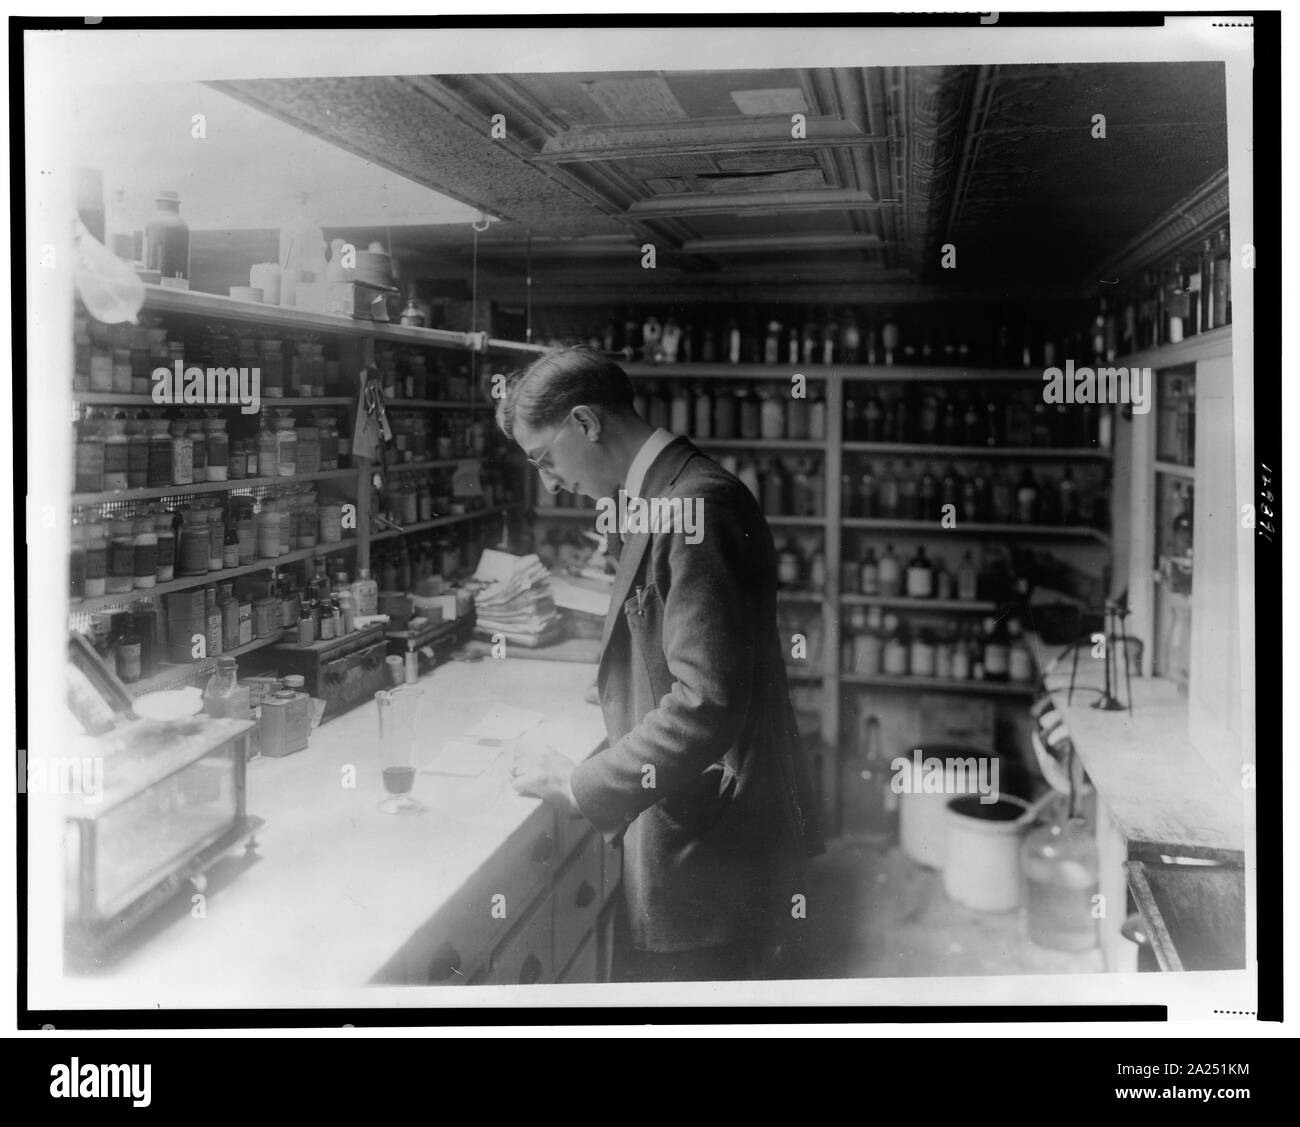

RM2A251KM–Il farmacista a persone di Drug Store, n. 5, 8 e H strade, N.E., Washington D.C., guardando a prescrizioni() sul contatore in camera rivestita con ripiani di bottiglie di farmacia